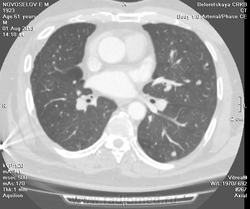

Мужчина оперирован по поводу BL щитовидной железы.Неоднократно проходил КТ в других лечебных учреждениях, у нас- впервые.Ставились заключения:MTS в лёгкие и лимф.узлы средостения слева.Образование слева увеличилось.Жалуется на одышку, не верит в заключение о MTS,просит узнать мнение других специалистов.

Метастазов в легкие не вижу. Похоже на лимфоузел в головке левого корня. Если позволите, запаздываете с началом исследования, плотность контраста в легочных артериях должна быть выше, чем а аорте. А одышка, не мудрено, легочная ткань диффузно уплотнена по типу "матового стекла", написал бы какую-нибудь интестициальную пневмонию, по типу альвеолита, может быть и гиперчуствительный пневмонит (не разберу есть или нет внутридольковые очажки), посмотреть бы изначально легочное окно, а не восстановленное из мягкотканного.

В диф. ряд: саркоидоз, атипичная форма.

Кажется,я понял,что Вы имели ввиду.Очажки стрелочкой указал.Согласен с тем,что очаги на фоне отображеничя сосудов кажутся фантазией,но они присутствуют.

Коллега, вынужден извинться и дезавуировать свой первый пост. Пересмотрел. Да, есть очаги, и они - вероятнее всего, метастазы.

Единственное,что напрягает,так это то,что эти изменения у пациента более 1,5 лет.А вид внешний у него не так уж и плох.А слева это всё-таки лимфоузел, а не периферическое образование в S3?

Думаю, да. Слишком близко лежит к легочной артерии.